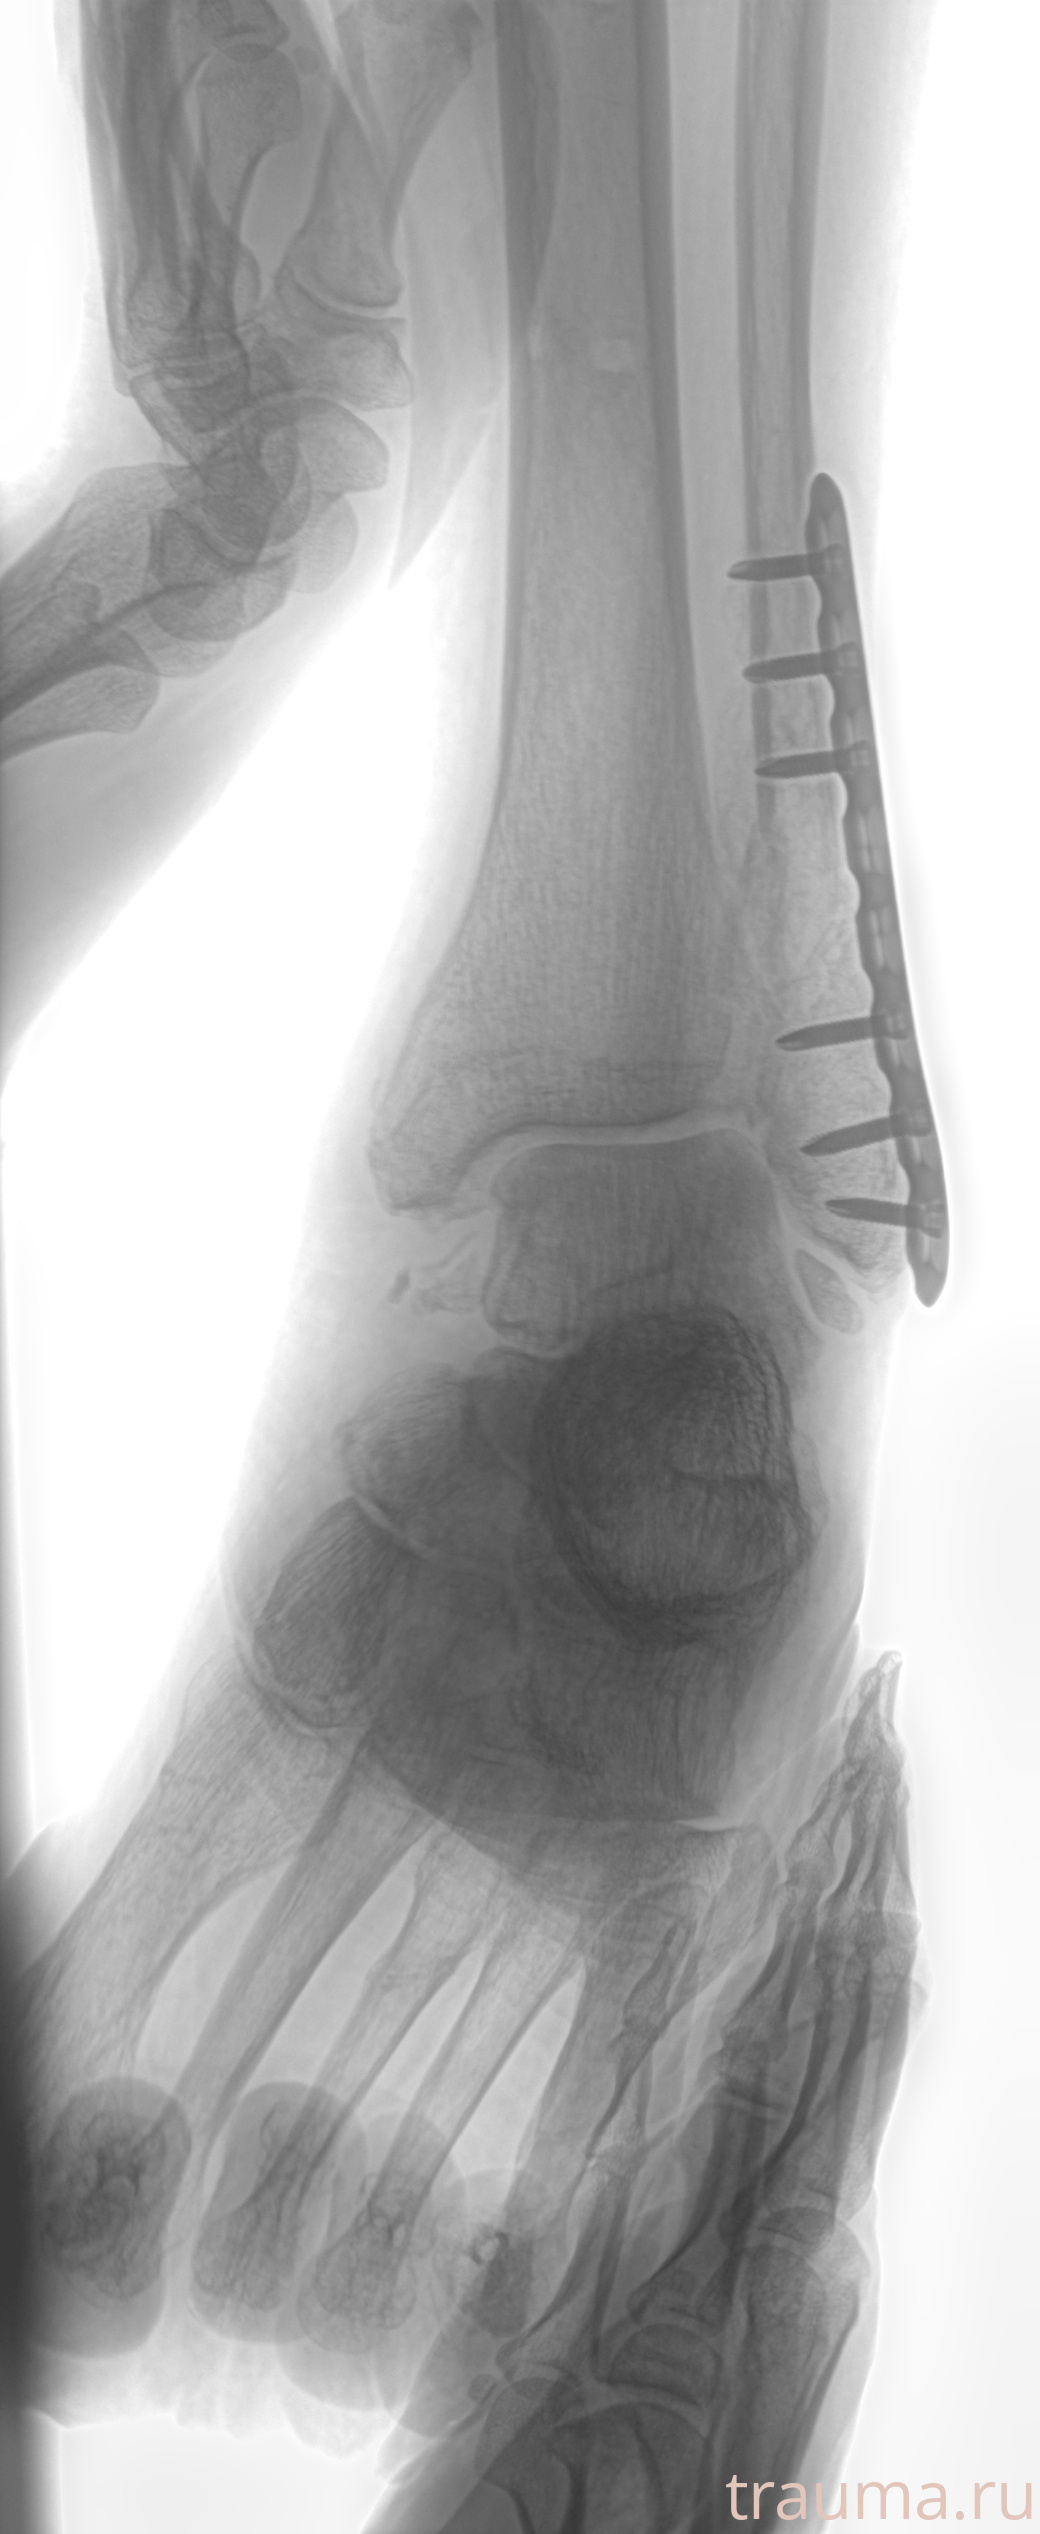

Рентгенограммы

Рентген на дому: по вашему адресу приезжает врач-рентгенолог, травматолог-ортопед с мобильным рентгеновским аппаратом, проводит диагностику травмы или заболевания, делает необходимые рентгенограммы, дает рекомендации по дальнейшему лечению. Получить качественные снимки в домашних условиях возможно благодаря уникальной методике, разработанной МосРентген Центром для института  Склифосовского